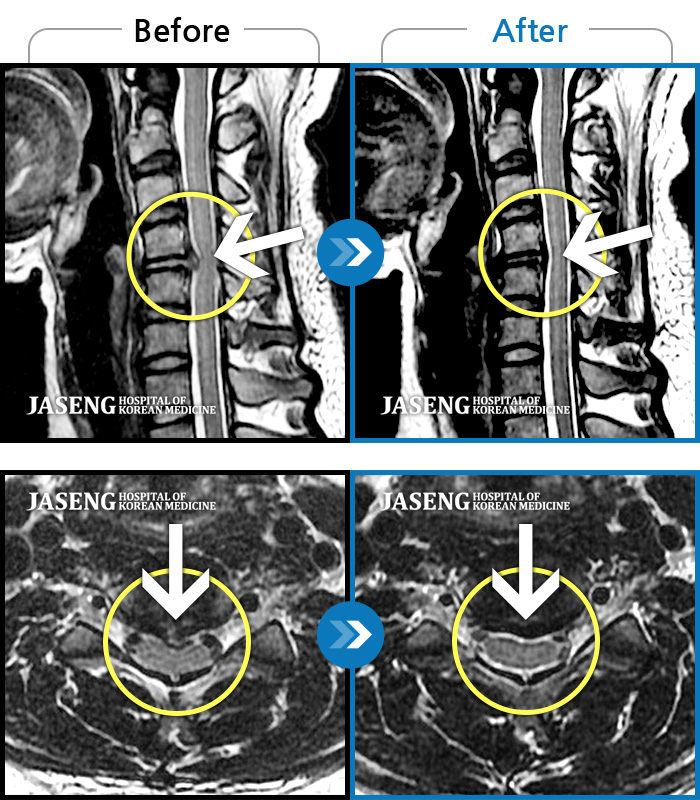

목디스크

부천 · 신동재 원장

운동 중 급격하게 발생한 후경부~좌측 어깨 및 좌측 상지 전반적인 저림이 있었다.

촬영시기

2021.10.26 ~ 2023.12.16

2024.01.05

조회수 478